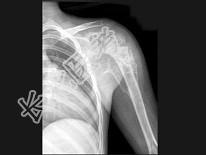

- 单项选择题男,28岁, 右上臂肿胀、疼痛,结合图像, 最可能的诊断是 ( )

A、骨肉瘤

B、成骨性骨转移瘤

C、化脓性骨髓炎

D、滑膜肉瘤

E、骨巨细胞瘤